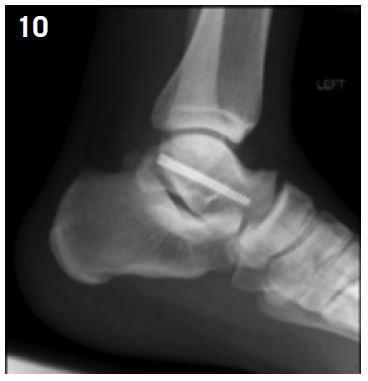

This fracture is rarely displaced, so its classification as a high-risk fracture is still controversial but due to the low vascularization of the talus, the significant risk of delayed union, and the high proportion patients unable to resume sport at the same level, for athletes surgical fixation is recommended even if the fracture is not displaced6,8,39 (Figure 10).

Figure 10: Talar body fracture fixation by simple screwing ( posterior apporach).